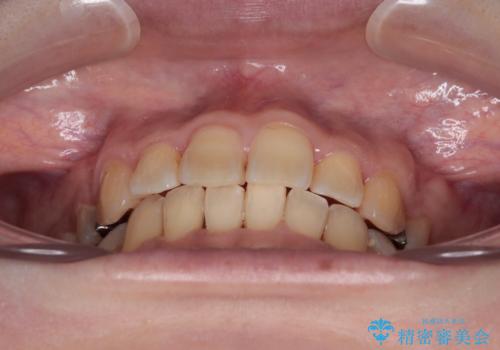

後戻りにリカバリーに少し時間を要しましたが、1年強の期間で無事に治療を終えることができました。